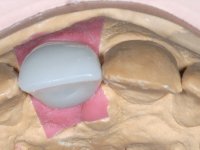

After performing an impression of the implant and making the models, we tested several rehabilitative options with the help of the implant brand planning kit. None proved capable. In this sense and as a resource solution, an innovative solution was proposed. It was proposed to make a milled Zr abutment with an appropriate design to receive a veneer that would hide the screw access hole. The veneer itself had a ceramic-coated Zr infrastructure. The goal was to achieve retention and strength by screwing the abutment and aesthetically solve the case with the veneer.

After the impression of the implant using a double-mix technique with double viscosity and the collection of shape and color information by the ceramist, we proceed with the work. In the model, a syn octa was placed over the implant, and a screw was placed on it to assess its emergence in relation to the incisal edge. Then, an adequate emergence profile in the artificial gingiva was prepared. A abutment with characteristics suitable for overbite and simultaneously capable of receiving a veneer was waxed on top of this scenario. This waxing gave rise to the manual milling of a very personalized abutment. An infrastructure in Zr was also made for the veneer with a very great adaptation to the abutment. On this infrastructure ceramics were placed. Ceramic fluorescence sought to compensate for the lack of fluorescence that Zr had and obviously further customize the aesthetics. The adhesive bridge was removed and the definitive work was placed. The syn octa was initially tightened with 35 N to the implant and then the Zr abutment was tightened over the syn octa with 15 N. The access hole was plugged and then the veneer was cemented with resin-reinforced glass ionomer. After 15 years, the patient returned to the consultation with tooth mobility. Fortunately, nowadays we have the possibility of having dynamic tightening wrenches that allow tightening screws with greater inclinations. An access cavity was made without damaging the incisal edge of the veneer. Tightening was done with a dynamic wrench with 15 N torque. The hole was covered with Teflon and filled with composite resin. This solution allowed the problem to be solved in a simple and economical way.